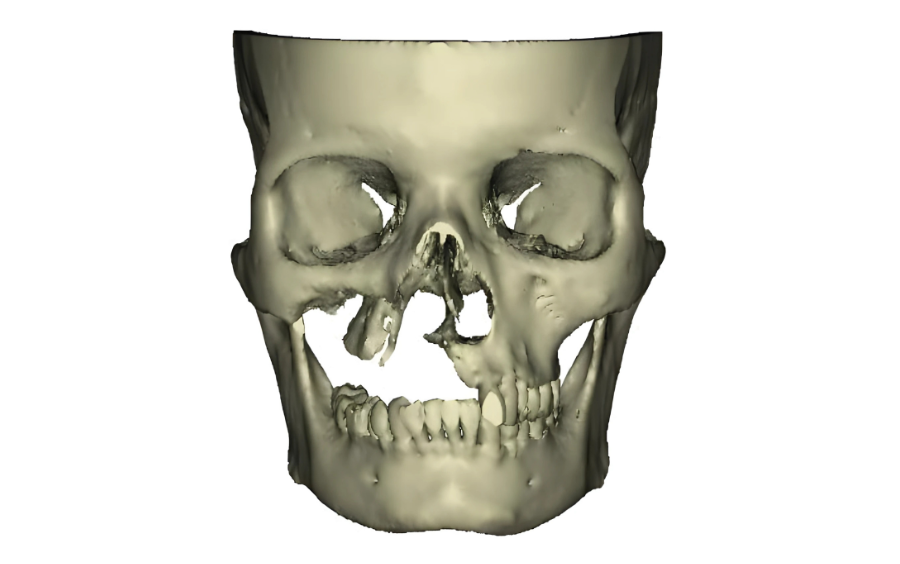

A 53 year old female, presented with a complex case of post-COVID Mucor-mycosis affecting her right maxilla and accompanying maxillary sinus.

approximately one year prior. Dr. Alka Trymbake, an MDS Oral & Maxillofacial Surgeon, diagnosed extensive mucormycosis in the right maxilla and maxillary

sinus through clinical and

radiological assessments.

Approximately one year later, Dr. Alka Trymbake collaborated with the design team at 3D Incredible to create and place a patient-specific implant. This implant was tailored to reconstruct the lost maxillary bone, aiming to enhance both facial aesthetics and functional restoration.

Implant was manufactured under ISO 13485 guidelines & evaluated to give an accurate fit & utmost safety. Once the resection was done, customized implant from 3D Incredible was implanted.